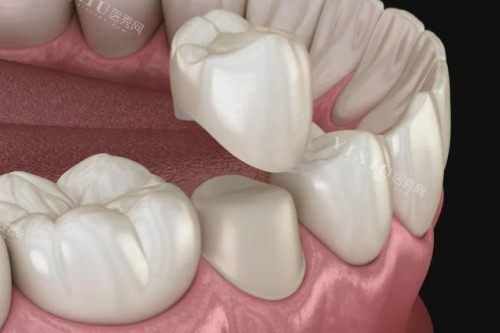

镶牙与牙冠项目

国产爱尔创全瓷牙冠:980 元起 / 颗

臻美全瓷牙冠:2500 元起 / 颗

烤瓷牙:800 元起 / 颗

全瓷贴面:2000 元起 / 颗

烤瓷冠桥修复:1200 元起 / 颗

活动义齿:1500 元起

全瓷牙冠生物相容性好,美观度高,价格相对烤瓷牙要贵一些。不同品牌和材质的牙冠在质量和性能上有所差异,从而导致价格不同。